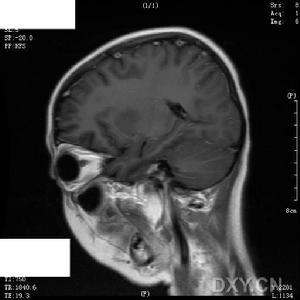

小兒病毒性腦炎--影像1.嗜睡